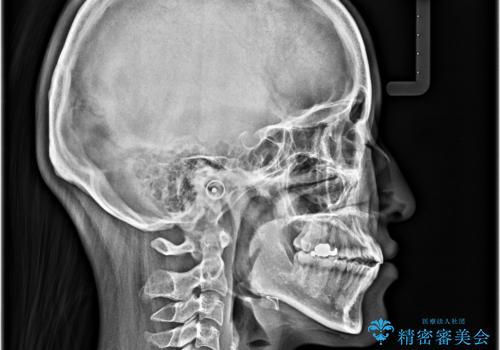

- 前歯の開咬を気にして来院された患者様です。

開咬の治療は、前歯を閉じるように動かすとともに、上下臼歯を圧下(骨内にめり込ませる)させることで進めて行きます。

インビザラインは臼歯の圧下を効果的に行えるため、インビザラインを用いて矯正治療を行うこととしました。

オープンバイトは舌の突出癖により誘発され、治療後も突出癖が残っている容易に後戻りしてしまいます。

治療期間を短縮するためにも、舌突出癖の改善が極めて重要となります。